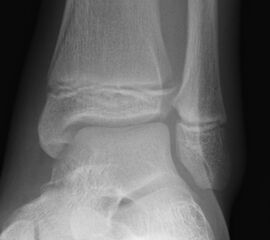

Fugengelenkfrakturen treten typischerweise vor dem 10. Lebensjahr auf, in einer Phase, in welcher die Wachstumsfugen noch weit offen sind. Dieser Frakturtyp betrifft fast ausschließlich den medialen Malleolus. Laterale Frakturen sind extrem selten, teilweise kommt es zu lateralen Bandverletzungen oder Fugenschaftfrakturen der distalen Fibula. Die Frakturlinie verläuft in einer Verlängerungslinie von der medialen Taluskante nach proximal. Häufig stellen sich Verletzungen des Innenknöchels im Röntgenbild schlechter dar, insbesondere wenn die Aufnahmen verdreht sind oder die Ebene der Fraktur bei geringer Dislokation verkippt zur Röntgenebene liegt. Besteht klinisch der geringste Hinweis auf eine Verletzung des Innenknöchels, muss aufgrund der Tragweite der Verletzung durch entsprechende Aufnahmen gegebenenfalls auch Schnittbildverfahren die Verletzung sicher diagnostiziert oder ausgeschlossen werden (Abb. 15).

Bei kindlichen Verletzungen des medialen Malleolus handelt es sich nach L. v. Laer um eine sogenannte Kadiläsion, d.h. eine Verletzung mit hohem Risiko eines schlechten Behandlungsergebnisses bei nicht korrekter Behandlung. Selbst bei optimaler Therapie ist das Risiko für spätere Wachstumsstörungen hoch, sodass diese Verletzungen nicht selten ein juristisches Nachspiel haben. Durch die Verletzung der wachstumsaktiven Zone kann es zu einem vorzeitigen Verschluss der Wachstumsfuge kommen, mit entsprechendem Fehlwachstum. Das Risiko eines vorzeitigen Verschlusses der Wachstumsfuge korreliert mit dem Ausmaß der Schädigung der wachstumsaktiven Zone. Ab dem 13. Lebensjahr wird das Risiko bei reduzierter Wachstumsaktivität zunehmend geringer.

Fugengelenkfrakturen können die Wachstumsfuge durchkreuzen (Abbildung 16a), ohne oder nur mit minimaler Beteiligung der Fuge sehr weit medial liegen (Abbildung 16b) oder durch die Fuge auslaufen (Abbildung 16c). Relevant für die Wachstumsprognose ist weniger die Form der Fraktur, sondern das Alter des Patienten zum Zeitpunkt des Traumas sowie das Ausmaß der Schädigung der Wachstumsfuge, wobei eine Korrelation mit dem Ausmaß der Dislokation besteht.